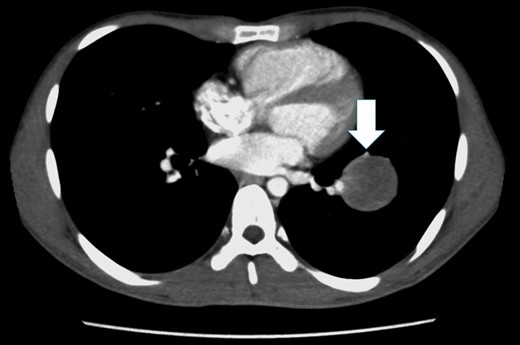

A 26-year-old man underwent arterial switch surgery for transposition of the great arteries in infancy. During a routine evaluation, a nodule was detected in the lower lobe of the left lung on chest computed tomography (CT). At the follow-up examination, the size of the tumor had increased 5 mm each year and he was referred for surgical treatment. Chest CT showed a 40-mm tumor with a smooth margin and a heterogenous inner structure in the left S8 pulmonary segment, close to the interlobar pulmonary artery (PA; Fig. 1). Tumor markers, such as carcinoembryonic antigen, cytokeratine 19 fragment and carbohydrate antigen 19-9, were within the normal range. Positron emission tomography (PET) showed abnormal F-18 fludeoxyglucose (FDG) uptake in the tumor shadow, and the maximum standardized uptake value was 4.66. There was no abnormal FDG uptake in the hilar or mediastinal lymph nodes. We planned to select the operative procedure using intraoperative frozen section examination, because it was difficult to diagnose whether the tumor was benign or malignant.

Chest CT shows a tumor with a smooth margin in the left S8 pulmonary segment, close to the interlobar PA, and the lingular segmental artery is compressed by the tumor (white arrow).